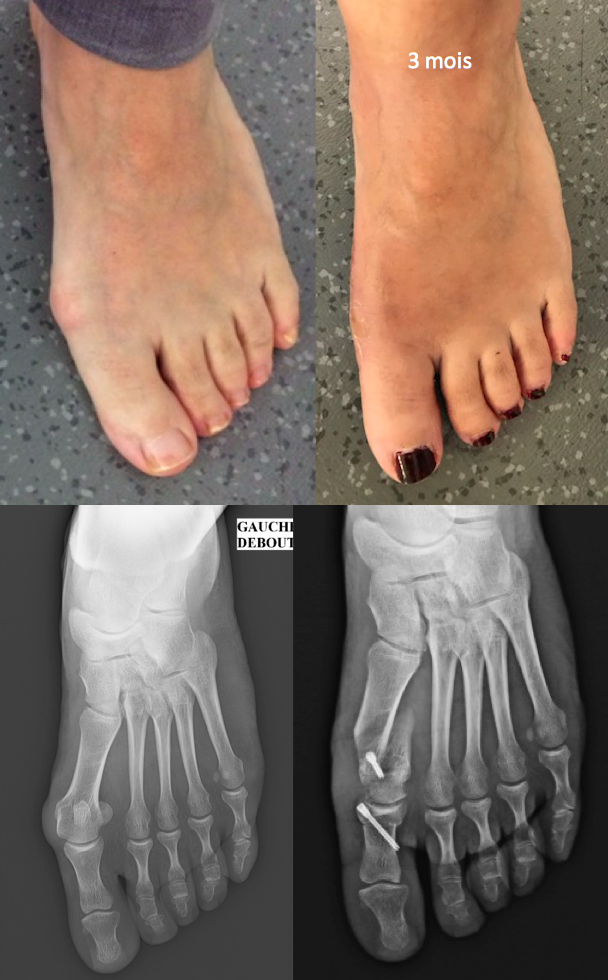

Aux différents degrés de déformation correspondent différentes techniques chirurgicales permettant de la corriger, de l’ostéotomie courte mini-invasive à l’arthrodèse métatarso phalangienne.

Voici quelques photos avant et 3 mois après la chirurgie :